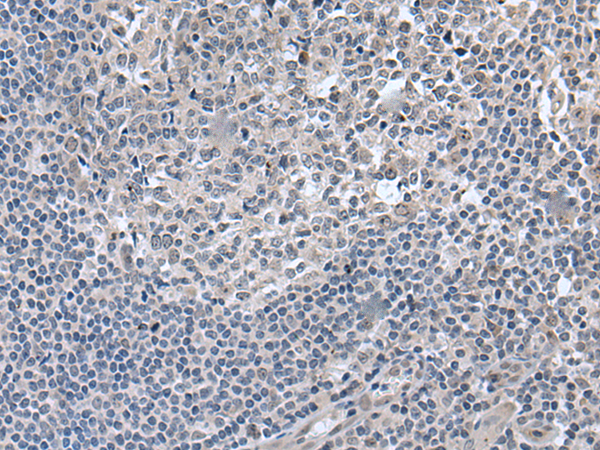

分类: 科研抗体货号: P02115别名: BCL7应用: IHC反应种属: Human, Mouse